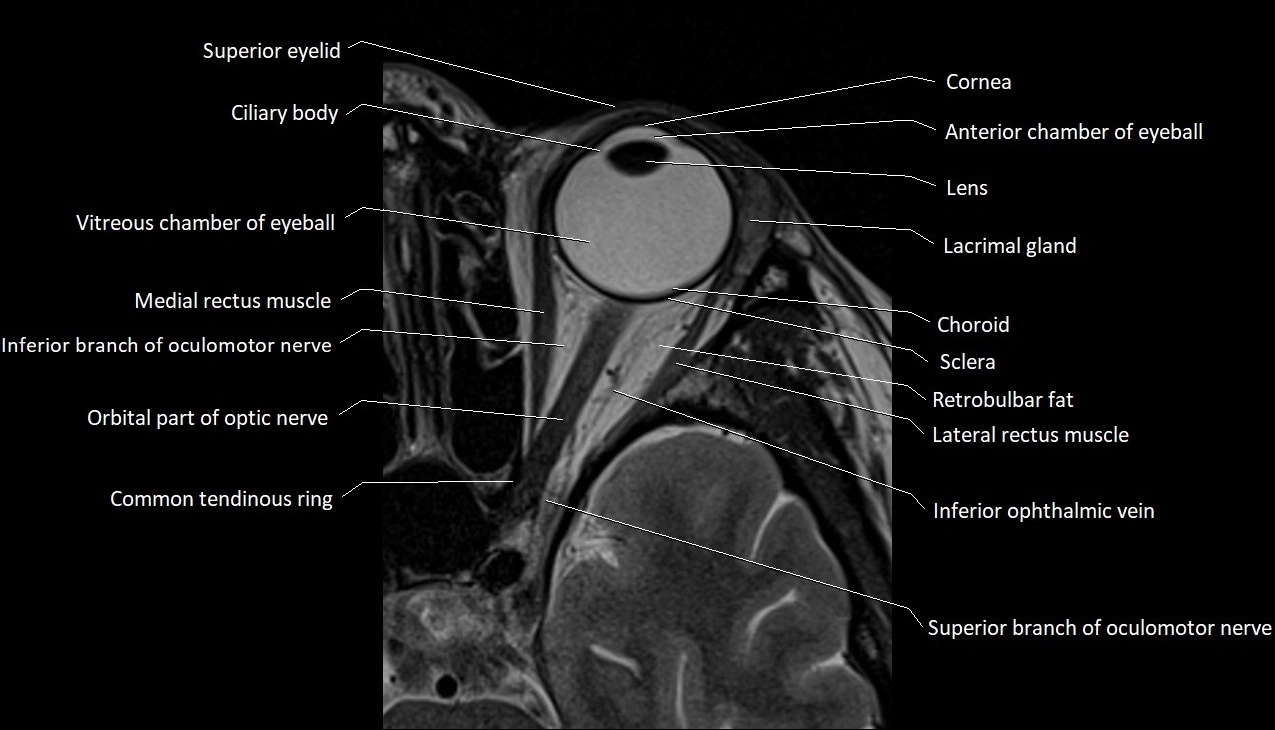

- Anterior chamber of eyeball

- Cornea

- lens of the eye

- Lacrimal gland

- Vitreous chamber of eyeball

- Medial rectus muscle

- Oculomotor nerve (inferior branch)

- Orbital part of optic nerve

- Common tendinous ring (Annulus of zinn)

- Lateral rectus muscle

- Inferior ophthalmic vein

- Oculomotor nerve (Superior branch)

- Choroid

- Sclera

- Retrobulbar fat

- Superior eyelid